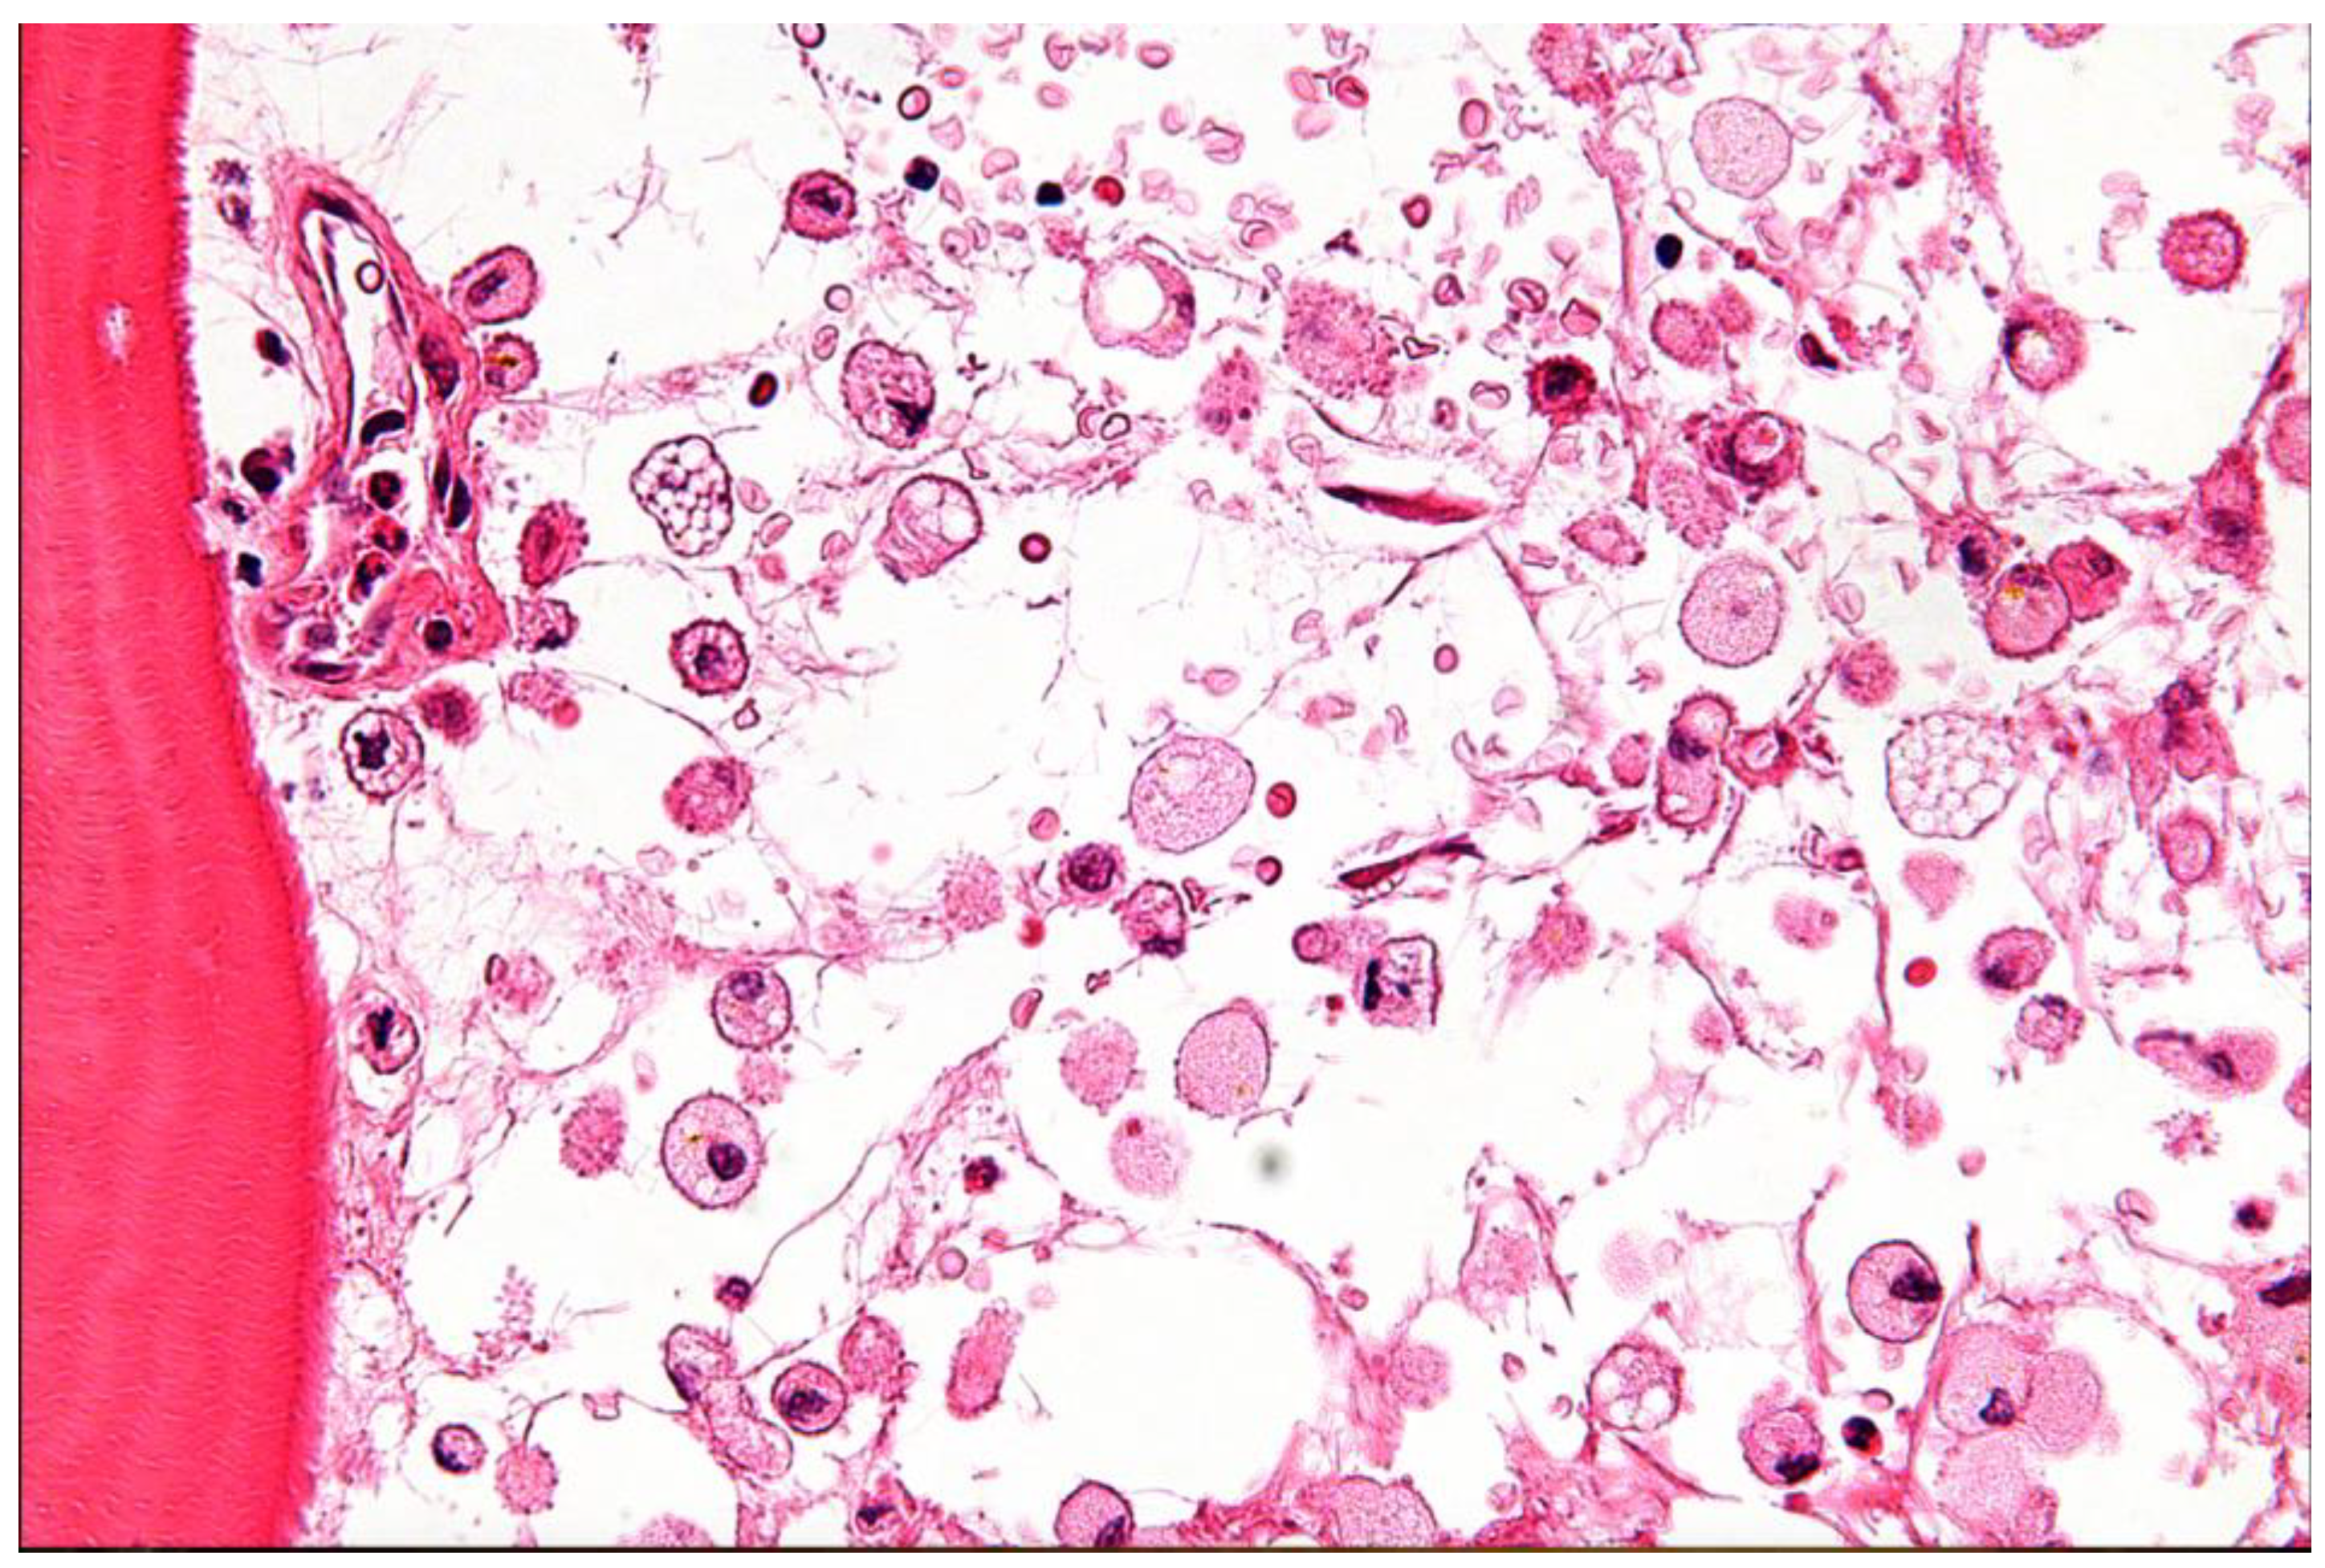

Despite these characteristic features, current diagnostic approaches for MELAS face several limitations. While elevated lactate levels in blood and CSF are common, this finding is not specific to MELAS and can be observed in a range of other mitochondrial diseases, metabolic disorders, or systemic illnesses [20,21,22]. Notably, a minority of individuals with MELAS may even present with normal serum lactic acid levels, further complicating diagnosis [20,21,22]. The genetic diagnosis of MELAS is complicated by mitochondrial heteroplasmy, which refers to the co-existence of mutated and normal mtDNA within the same individual. The clinical expression of MELAS is highly dependent on the proportion and tissue distribution of the mutated mtDNA [20,21,22]. This phenomenon means that the pathogenic mtDNA variant may be undetectable in readily accessible samples, such as leukocytes, often necessitating genetic testing from other tissues, including buccal mucosa, urinary sediment, or skeletal muscle [20,21,22]. This variability in mutational load across tissues can lead to false-negative results if only blood samples are analyzed [20,21,22]. Furthermore, while a muscle biopsy revealing ragged red fibers (RRFs) is suggestive of mitochondrial myopathy, it is not always a mandatory or definitive diagnostic criterion, as biochemical results from muscle tissue can sometimes appear normal despite the presence of MELAS (Figure 4 and Table 1) [20,21,22]. Neuroimaging, such as MRI, may reveal stroke-like lesions that do not conform to typical vascular territories; however, these findings are also not unique to MELAS and can be observed in other conditions [20,21,22].

25. File:Modified Gomori trichrome stain showing several ragged red fibers.jpg. Wikimedia Commons. https://commons.wikimedia.org/w/index.php?title=File:Modified_Gomori_trichrome_stain_showing_several_ragged_red_fibers.jpg&oldid=763868130. Published May 16, 2023. Accessed June 30, 2025.